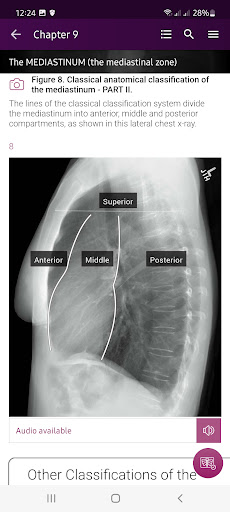

Section II* introduces the concept of radiological zones to give you a starting point in the understanding of the radiological anatomy of the chest. The next chapters review in detail the radiological anatomy of specific anatomical structures, also provide examples of how the x-ray image can change due to pathology. The final chapter explains how the individual structures come together to form the radiological image.